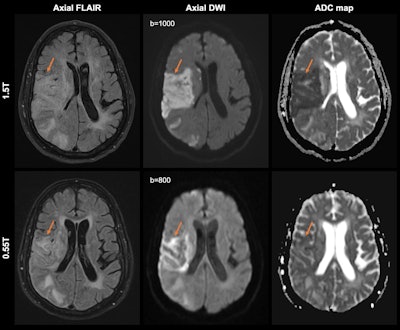

Acute right middle cerebral artery territory infarction (arrows) in a 66-year-old man, imaged at 1.5-tesla first and then at 0.55-tesla nine days later. Initial 1.5-tesla MRI images (top row) show diffusion restriction with associated mild T2 prolongation, compatible with acute infarction. On the subsequent 0.55-tesla images (bottom row), there is expected evolution of the infarct, with normalization of the apparent diffusion coefficient (ADC) map. Acquisition times for FLAIR imaging were 2 minutes, 45 seconds (with deep learning reconstruction) for 1.5-tesla imaging and 4 minutes, 14 seconds for 0.55-tesla imaging. The acquisition times for DWI were 1 minute, 3 seconds for 1.5-tesla imaging and 2 minutes, 52 seconds for 0.55-tesla imaging. Images and caption courtesy of the RSNA.Acute right middle cerebral artery territory infarction (arrows) in a 66-year-old man, imaged at 1.5-tesla first and then at 0.55-tesla nine days later. Initial 1.5-tesla MRI images (top row) show diffusion restriction with associated mild T2 prolongation, compatible with acute infarction. On the subsequent 0.55-tesla images (bottom row), there is expected evolution of the infarct, with normalization of the apparent diffusion coefficient (ADC) map. Acquisition times for FLAIR imaging were 2 minutes, 45 seconds (with deep learning reconstruction) for 1.5-tesla imaging and 4 minutes, 14 seconds for 0.55-tesla imaging. The acquisition times for DWI were 1 minute, 3 seconds for 1.5-tesla imaging and 2 minutes, 52 seconds for 0.55-tesla imaging. Images and caption courtesy of the RSNA.